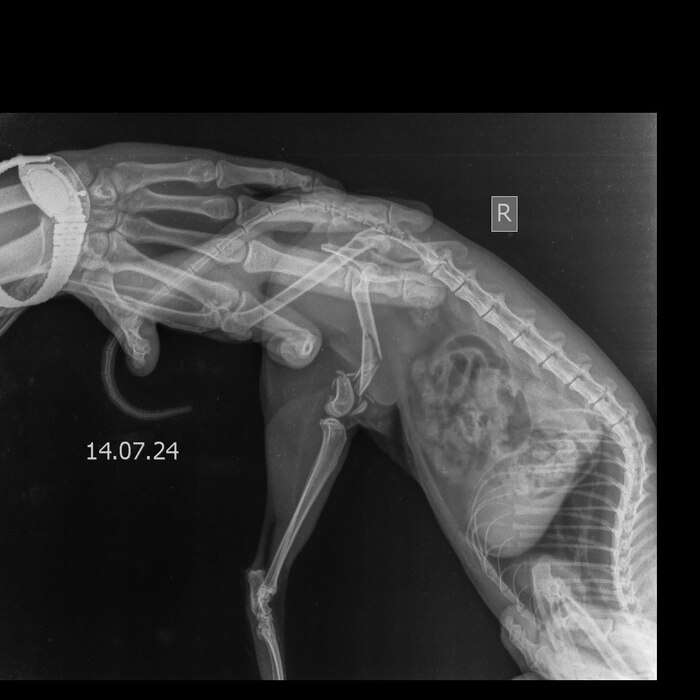

Пока кошка Милка от которой отказались ее же хозяева продолжает лежать у нас, сегодня был разговор со стоматологом.К сожалению стоматолог находится в другой клинике и не может приехать осмотреть животное, но он попросил сделать снимки записать видео, что бы предположить хотя бы какой диагноз у кошки.

После этих манипуляций был поставлен пока предварительный диагноз: Вывих височно- нижнечелюстного сустава?Перелом нижней челюсти по симфизу?

Стоит оговорится, что пока все предварительно, более точный диагноз он скажет когда осмотрит кошку. В пятницу 19 числа будет проведена операция- остеосинтез, во время операции стоматолог и осмотрит челюсть, и скажет свой вердикт.

Прикладываю рентгены кошки